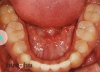

partial braces